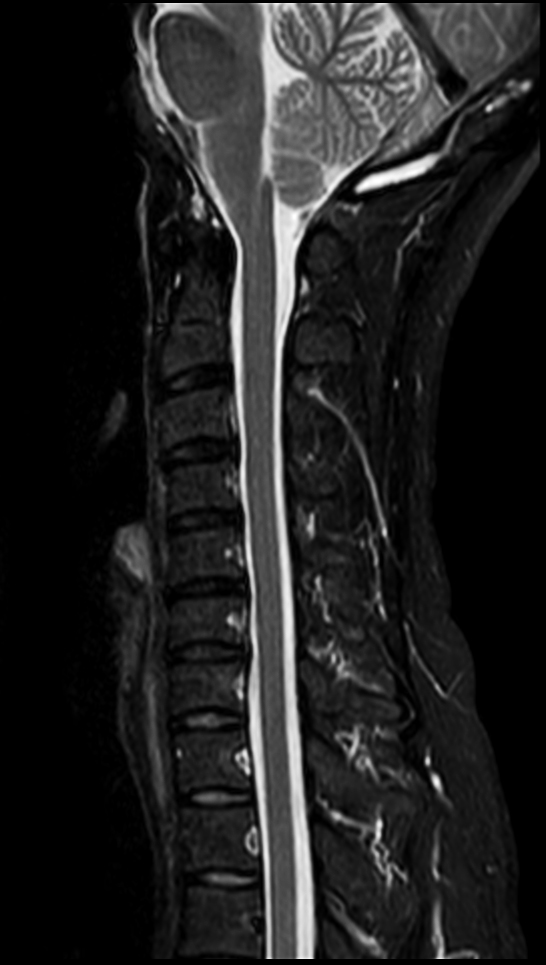

Sagittal T2w mDIXON TSE (In Phase)

Sagittal T2w mDIXON TSE (Water)